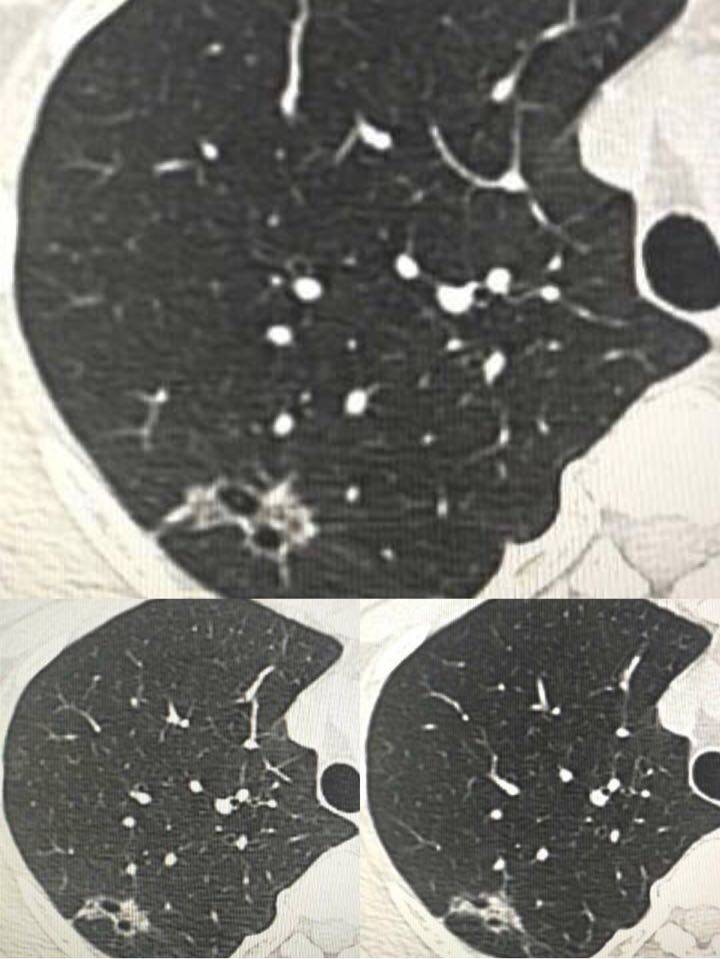

再看第二位患者,简称希望,大家看她的图跟第一位患者的几乎如出一辙,但陈医生第一次却只建议她定期复查

她们两位提供的病灶,都可以称为磨玻璃影,就像玻璃上被砂纸磨过,留下很粗糙的一片。

同时邻近胸膜的地方,都有点牵拉,就是胸膜局部有牵拉出一点。

大家仔细看一下两位的胸膜牵拉,月半弯的比较锐利,拉扯出来的部位呈三角形。而希望的片子里,拉扯出来的部位没那么锐利,绝呈一点不规则的方形。

而希望觅友的胸膜牵拉呢,则比较接近方形,最重要的是,没有症状,体检发现的。所以陈医生最初建议她定期复查。

但是,随着了解的深入,陈医生翻脸了,让她抓紧去手术。为什么呢?大家看看讨论截图就明白了。